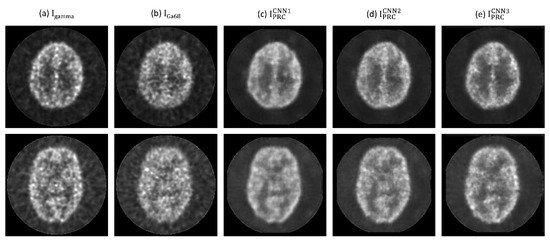

3. Results